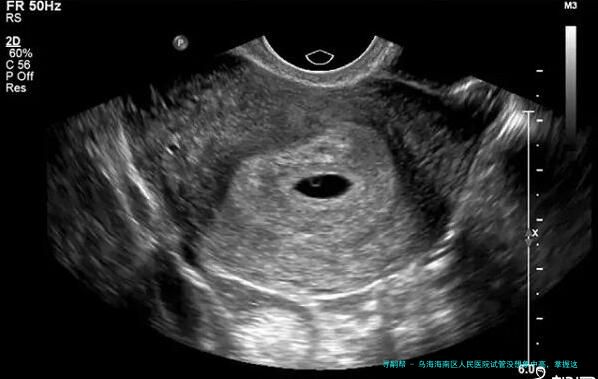

目前在乌海海南人民医院暂做不了试管婴儿助孕,关于在乌海市内的不孕不育病人来说,可以就近到乌海妇幼保健院就诊。不管在哪里个生殖医院做试管,其步骤方法有进周促排、取卵取精、胚胎培养、检查与移植等,为容易于众人认知乌海试管费用情况,这里就有一份有关乌海试管婴儿的费用明细单明细: